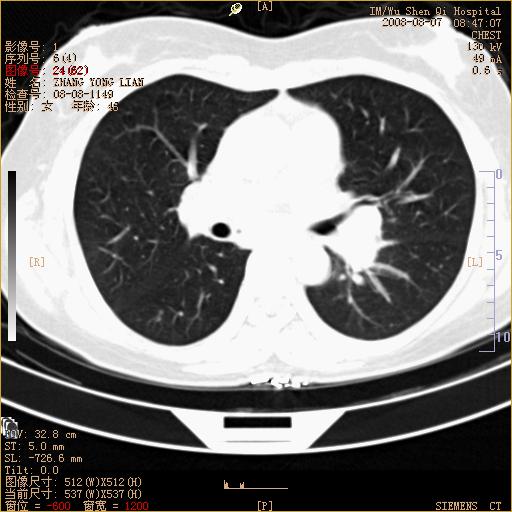

标题: CT15050:女,46岁,咳嗽胸痛一月余 [打印本页]

纵隔窗没发全,左下肺近胸膜处结节。有长毛刺,纵隔淋巴结增大,不排除恶性病变。

考虑肺癌

考虑左肺下叶后基底段周围型肺癌伴纵隔淋巴结转移可能性大。

左下肺ca并纵隔及左肺门区淋巴结转移。

1)考虑左肺下叶后基底段周围型肺癌伴纵隔淋巴结转移。2)脾内低密度灶,性质待定;不排除转移瘤可能。